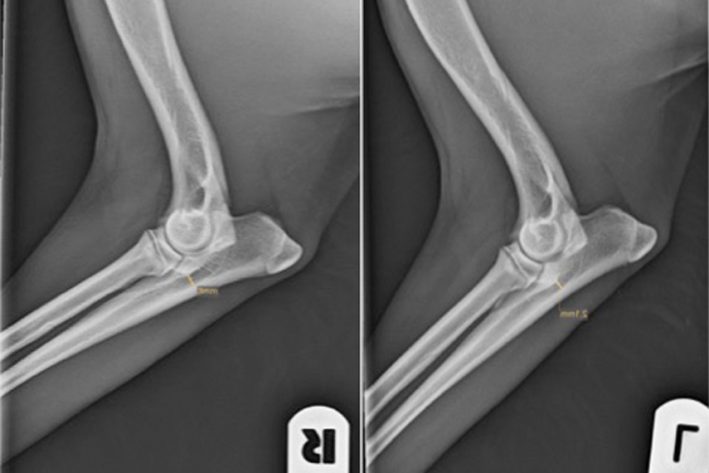

Isolierter Proc. Anconeus

Isolierter Proc. Anconeus Nach Anheilung